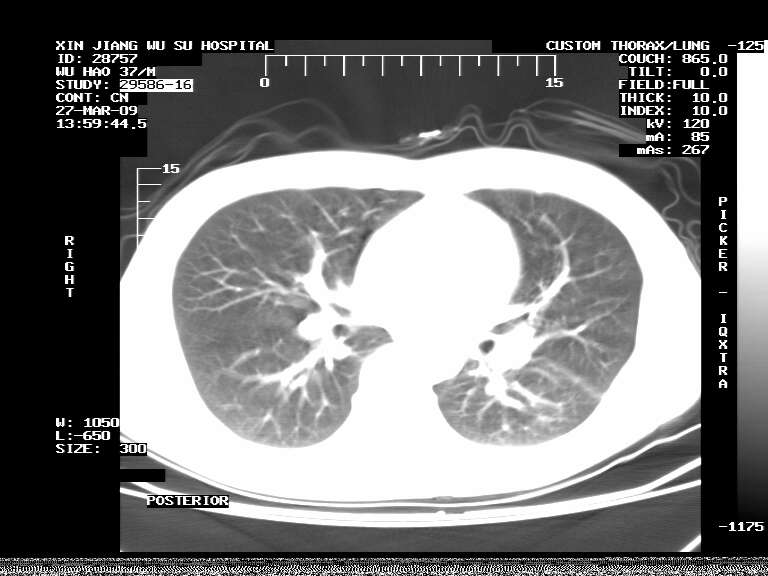

男,37岁,体检胸透发现阴影。

患者体检发现 无症状 左肺下叶占位,边缘模糊,可见血管聚束、分叶、胸膜牵拉,增强呈不均匀性强化。 首先考虑左肺下叶周围型肺癌,建议穿刺活检。

左肺下叶见一结节病变,边缘欠清不光滑,与胸膜粘连且胸膜局限性增厚,注药后呈环形强化,动脉期壁呈明显点环状强化,静脉期壁强化减低,中心密度低无强化,灶周无明显的卫星灶和水肿区(晕征)---考虑周围性肺癌,不除外感染性病变,建议穿刺活检。

周围有卫星灶,胸膜反应不明显,病灶中心有坏死。建议先抗结核治疗后,短期复查

左肺下叶大片实变影,内靠胸膜见不规则更高密度结节灶,边缘强化,相邻胸膜增厚,胸膜下脂肪线存在。考虑炎症,结核可能。